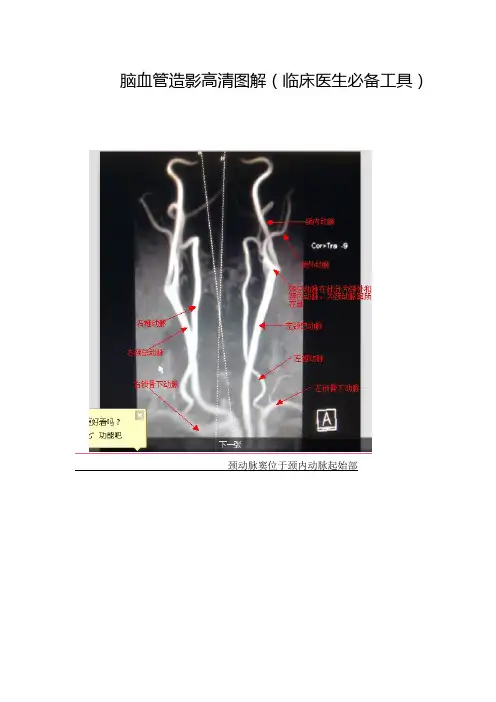

脑血管造影高清图解(临床医生必备工具)

颈动脉窦位于颈内动脉起始部

右侧颈内动脉DSA(正常)

左侧颈内动脉DSA (正常)

左侧椎动脉DSA(正常)

右侧椎动

脉DSA (正常) 病例

左侧椎动脉起始段未显影,v2末端、v3段、v4起始段显影,v4上段及基底动脉未显影,左侧锁骨下动脉起始段斑块行成。

()

右侧颈总动脉起始段显影,右侧颈总动脉上段及右侧颈内动脉、颈外动脉未显影。

(右侧颈总动脉、颈内动脉闭塞)

左侧颈内动脉仅见一残端

右侧椎动脉造影:见右侧椎动脉、基底动脉、双侧大脑后动脉、双侧小脑上动脉、双侧小脑

下动脉、右侧小脑下后动脉显影,双侧大脑后动脉分支向双侧大脑前动脉、大脑中动脉供血区代偿供血

左侧颈内动脉闭塞,左侧颈外动脉分支向脑内代偿供血。